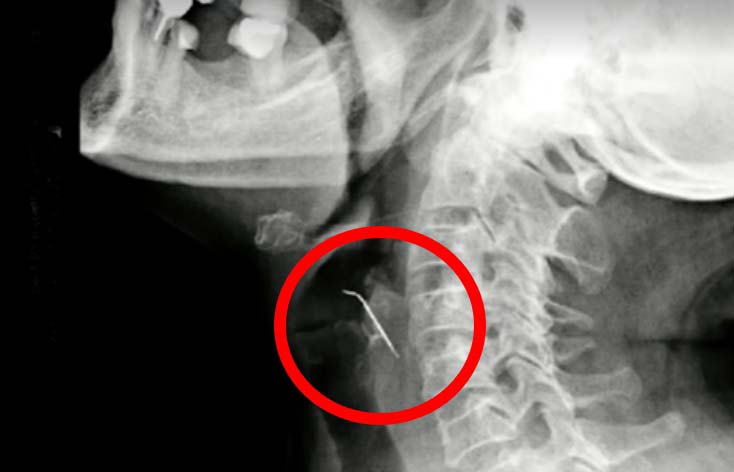

엑스레이 검사 결과, 뾰족한 물체가 셀리아의 경동맥을 관통하고 있는 것으로 확인됐다. 추후 수술을 통해 밝혀진 물체의 정체는 날카로운 못이었다. 못이 어떻게 과자에 들어갔는지는 확인되지 않았다. 셀리아는 “목에 뼈가 박혔다고 생각해 병원에 갔다”며 “못이나 철사 조각 같은 게 있을 것이라고는 생각하지 못했다”고 말했다.